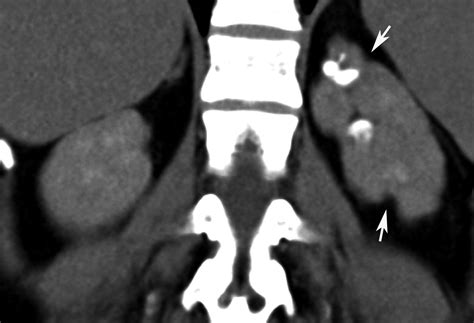

Renal parenchymal disease can cause hypertension, haematuria, proteinuria and also urinary tract infection.the patient presents with various clinical symptoms like colicky pain in lumbar region (renal colic), swelling on the feet and face, fatigue, loss of appetite, nausea, vomiting, itching, metallic taste. Junctional parenchymal defects in renal imaging are a normal variant, which results from the incomplete embryonic fusion of renunculi. Fig tea cures parenchymal disease symptoms. Most primary renal diseases eventually disturb sodium and volume control sufficiently to produce clinical as discussed, parenchymal renal disease may refer to either unilateral (uncommon) or bilateral conditions. Studies estimate that up to 50% of patients diagnosed with lupus erythematosus experience a renal parenchymal disease known as lupus nephritis. What are the symptoms/treatment/diet for renal parenchymal disease? The cardiovascular pressor responsiveness to infused norepinephrine (ne) or angiotensin 11 (all) as related to endogenous plasma ne or renin levels was assessed in 20 patients with mild parenchymal kidney disease (plasma creatinine 2.20 0.58 mg/dl A:due to limited information including the lack of blood test results (namely serum creatinine), it is difficult to comment on the above findings probably noted in a radiological imaging.

Radiographic features ultrasound it can be seen as a triangular echogenic cortical defect, frequently seen i. Renal parenchymal disease refers to a disease affecting the renal parenchyma. Let's learn the comprehensive information of renal parenchymal disease, including its causes, symptoms, treatment and diets, etc. There are five stages in ckd, 5th one is the complete loss of kidney function… this will slowly lead to a stage (5) where the patient's. Patients with chronic renal diseases (glomerulonephritis, pyelonephritis) complain on general weakness, fatigue in development of functional disorders. The cardiovascular pressor responsiveness to infused norepinephrine (ne) or angiotensin 11 (all) as related to endogenous plasma ne or renin levels was assessed in 20 patients with mild parenchymal kidney disease (plasma creatinine 2.20 0.58 mg/dl Once renal parenchymal disease develops, kidneys lose its ability to remove the waste products from the blood, causing various symptoms. This is often seen during the. Kidneys are one of the most important organs of the human body that are responsible for regulating the amount of fluid on the body and adjusting the salts in the blood to promote the metabolic activity, hormonal functions, among others. Renal parenchymal disease can be chronic as well as acute. Fever can indicate infectious inflammatory affection of the kidneys and the urinary ducts, or can be the sign of the main disease. Renal parenchymal disease includes diseases that damage the innermost region of the kidney where leakage of urine occurs. Many causes can trigger the damaged in renal parenchyma, including.